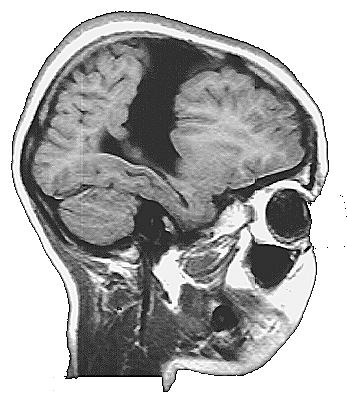

As crianças ARM e KTG são portadoras de lesões cerebrais denominadas Esquizencefalia (Fig. 5 e 6), que são decorrentes de distúrbios no processo embriogênico, que ocorrem no primeiro trimestre da gravidez. As lesões no indivíduo ARM se localizam no lobo frontal esquerdo e incluem também a ausência do septo pelúcido. Já a criança KTG tem as lesões localizadas no lobo parietal direito e também mostra sinais de comprometimento do hipocampo direito.

Os MAREs de todos os indivíduos mostram uma atividade cerebral coerente com a lesão encontrada nas correspondentes MRIs. Assim, por exemplo, ARM tem uma lesão frontal esquerda na MRI, que está associada á um silêncio funcional nas derivações frontais esquerda nos seus MAREs (Fig. 5). Já o indivíduo WA tem uma lesão que se localiza predominantemente no lobo parietal esquerdo, que está associada a uma ausência de atividade nas derivações C3 e P3 nos seus MAREs mostrados na fig. 5. Finalmente, a lesão de KTG se localiza principalmente no lobo parietal direito, que se reflete nos correspondentes MAREs, por uma diminuição da ativação, principalmente, nas derivações P4 e T6.

K.T.G 10 a. Esquizence-faliaLobo Parietal |

Fig. 6 Lesão no hemisfério direito

O quadro eletroencefalográfico de KTG associado ao processamento verbal é totalmente distinto daqueles registrados nos indivíduos ARM e WA. Aqui observa-se uma ativação maior nas derivações F7, T3 e C3, no hemisfério esquerdo, durante as primeiras frases das charadas. Esta atividade se reduz um pouco na fase final da charada. Durante as duas etapas observa-se uma ativação de áreas frontais direitas, mas nunca das regiões temporoparietais do hemisfério direito.

As lesões de KTG se restringem ao hemisfério direito. Nesse caso, a participação do hemisfério esquerdo no processamento verbal fica claramente demonstrada nos MAREs apresentados na fig. 6. KTG é capaz de uma boa compreensão da linguagem, como demonstra seu bom rendimento nos jogos de linguagem. A pobreza de seu uso da linguagem expressiva está relacionado ao sua deficiência mental. Aliás, a inclusão de KTG nesse trabalho tem por finalidade apresentar um padrão de comparação para as crianças ARM e WA, também portadoras de deficiência mental. Dessa maneira, pode-se ressaltar que a plasticidade neural é a responsável pela capacidade de linguagem nessas duas crianças, e que a eventual pobreza do uso da linguagem que elas fazem, está mais associada à uma menor capacidade de processamento cerebral, devido à sua deficiência mental, do que às lesão específicas das áreas verbais do hemisfério esquerdo.